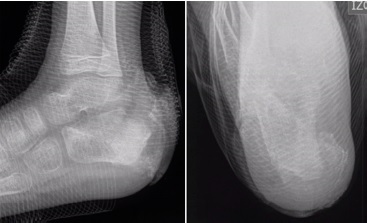

La radiografía convencional fue examen de rutina en todos los pacientes del estudio. Evidenció hallazgos inespecíficos en 5 de 9 pacientes consistentes en edema de tejidos blandos. En uno de esos casos se apreciaron lesiones óseas en el calcáneo (Figura 1). La TC se utilizó como complemento en un caso para confirmar un defecto óseo cortical secundario a la infección (Figura 2).

La RM se realizó en 6 pacientes con hallazgos sugestivos de osteomielitis en 5 de ellos (Figura 3).